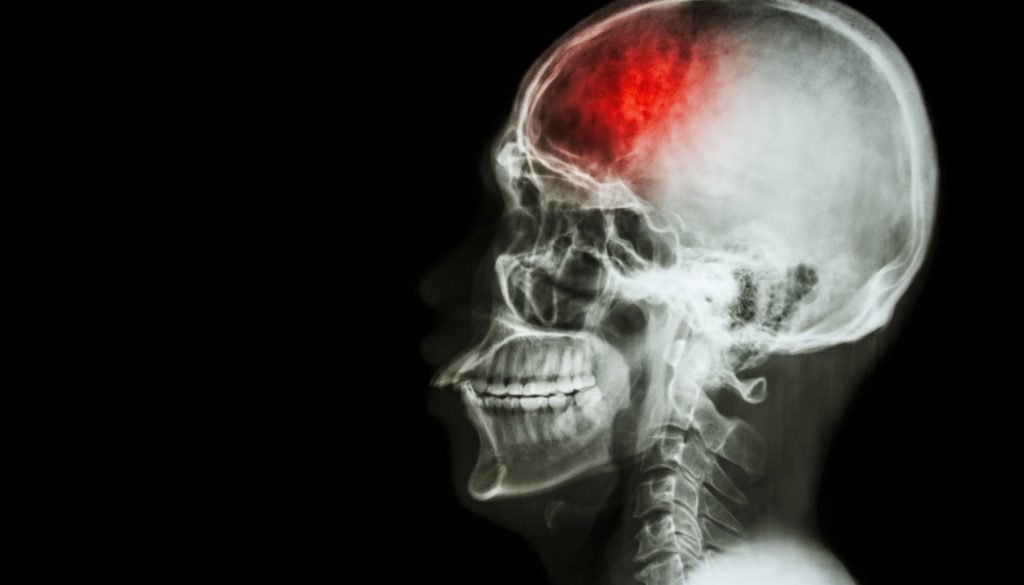

السكتة الدماغية تحدث عندما ينقطع تدفق الدم إلى جزء من الدماغ، ما يؤدي إلى تلف في الخلايا الدماغية. هناك نوعان رئيسيان من السكتات الدماغية:

تحدث عندما تنفجر الأوعية الدموية في الدماغ، مما يتسبب في تسرب الدم إلى الأنسجة المحيطة.